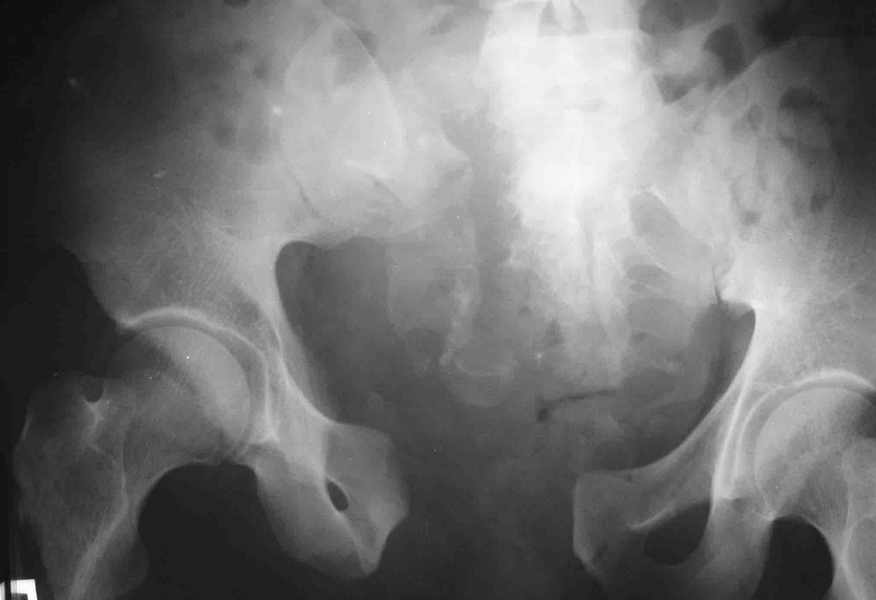

Re: разрыв лонного сочленения

Вот вариант решения похожей ситуации